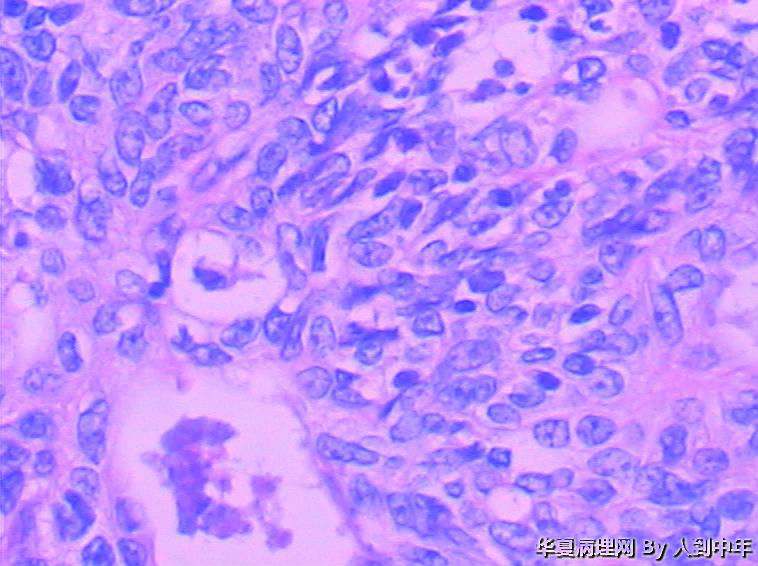

患者,男性,72岁,右肺中叶占位,肺门部肿物,散在多结节状,直径0.2-2.2cm。

没见过,我们也没有免疫组化,全靠HE。临床就想诊断了肿瘤让患者出院,我还想让患者去肿瘤会诊?大家怎么诊断?遇到临床不想会诊这种情况又如何办?

NT。需计数分裂像分级。

低分化癌,看到有腺样结构,肿瘤多结节,也要排除转移。

低分化癌,可能伴神经内分泌分化。不能标记也要建议会诊,去不去是他们的事

微囊、细胞梭形或立方、癌巢周边细胞见栅栏状(图22),不能排除基底细胞样癌。

癌,微囊、细胞梭形或立方、癌巢周边细胞见栅栏状,不能排除基底细胞样癌。多结节,也要排除转移性涎腺型恶性肿瘤,腺样囊腺癌等。